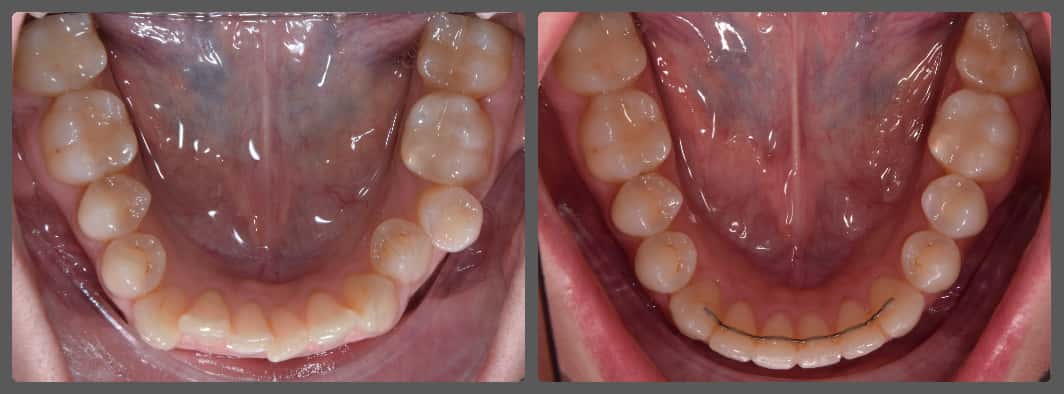

Balázs súlyos alsó torlódása miatt keresett fel magánrendelésemen. A diagnosztikus vizsgálatok során előbbin túl alsó-felső fogívszűkületet, valamint nyitott harapási hajlamot állapítottam meg. Kezelését Pitts21 alsó-felső rögzített fogszabályozó készülékkel kezdtük meg. A nyitott harapási hajlamot a hátsó fogakra helyezett harapásemelővel kontrolláltuk. A torlódott fogaknak tolórugóval és interproximális redukcióval teremtettünk helyet, és intermaxilláris gumihúzással tökéletesítettük a harapást. A fogszabályzó kezelés teljes időtartama alatt Balázs 110%-osan együttműködő volt, ezért 21 hónap alatt sikerült kiemelkedő végeredményt elérnünk.